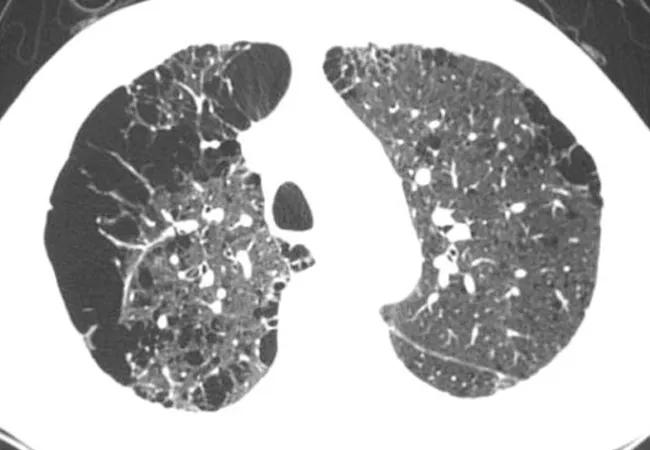

Pure ground-glass nodules

For patients with pure ground-glass nodules (GGNs) smaller than 6 mm in diameter, no routine follow-up is generally recommended. However, the revised guidelines include an optional two to four year follow-up in selected subjects with nodules close to 6 mm or those with clinical or radiographic features that place them at higher risk. This somewhat ambiguous recommendation was prompted by recognition that 10 percent of such nodules can grow and that 1 percent may progress to adenocarcinoma over many years.

For patients with pure GGNs > 6 mm, follow-up at six to 12 months and then every two years until five years is recommended, given that some of these nodules represent indolent adenocarcinomas (3 percent in one large screening study).

Solitary, part-solid lung nodules (PSNs)

Depending on the size of the solid component, PSNs can represent adenocarcinoma in situ, minimally invasive adenocarcinoma or invasive adenocarcinoma. For this reason, a follow-up CT at three to six months and then annually for five years is recommended for all PSNs ≥ 6 mm. PSNs with suspicious morphology, growing solid component or solid component > 8 mm should be evaluated with a PET/CT, biopsy or resection.